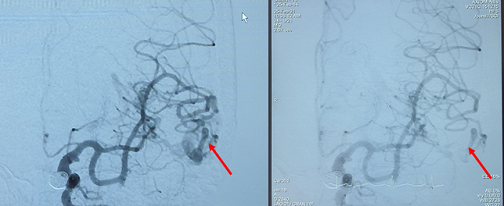

Tháng 2/2021, Bệnh nhân nữ D.T.S, 56 tuổi có triệu chứng đau đầu nên đi khám và điều trị nhiều nơi nhưng vẫn còn đau đầu. Gần đây bệnh nhân cảm thấy đau đầu nhiều hơn, nói khó, ngất xỉu nên được gia đinh đưa đi khám. Tại Bệnh viện Trường Đại học Y Dược Cần Thơ, bệnh nhân được đánh giá tri giác tỉnh táo, có yếu kín đáo ½ người phải, nói khó nên được các bác sĩ chuyên khoa hội chẩn và chỉ định chụp cộng hưởng từ sọ não để chẩn đoán. Kết quả chụp cộng hưởng từ sọ não phát hiện bệnh nhân bị xuất huyết não do vỡ khối dị dạng động tĩnh mạch não ở thái dương (T).

Hình 1: Hình chụp cộng hưởng từ phát hiện xuất huyết não (A) và khối dị dạng động tĩnh mạch não (B)